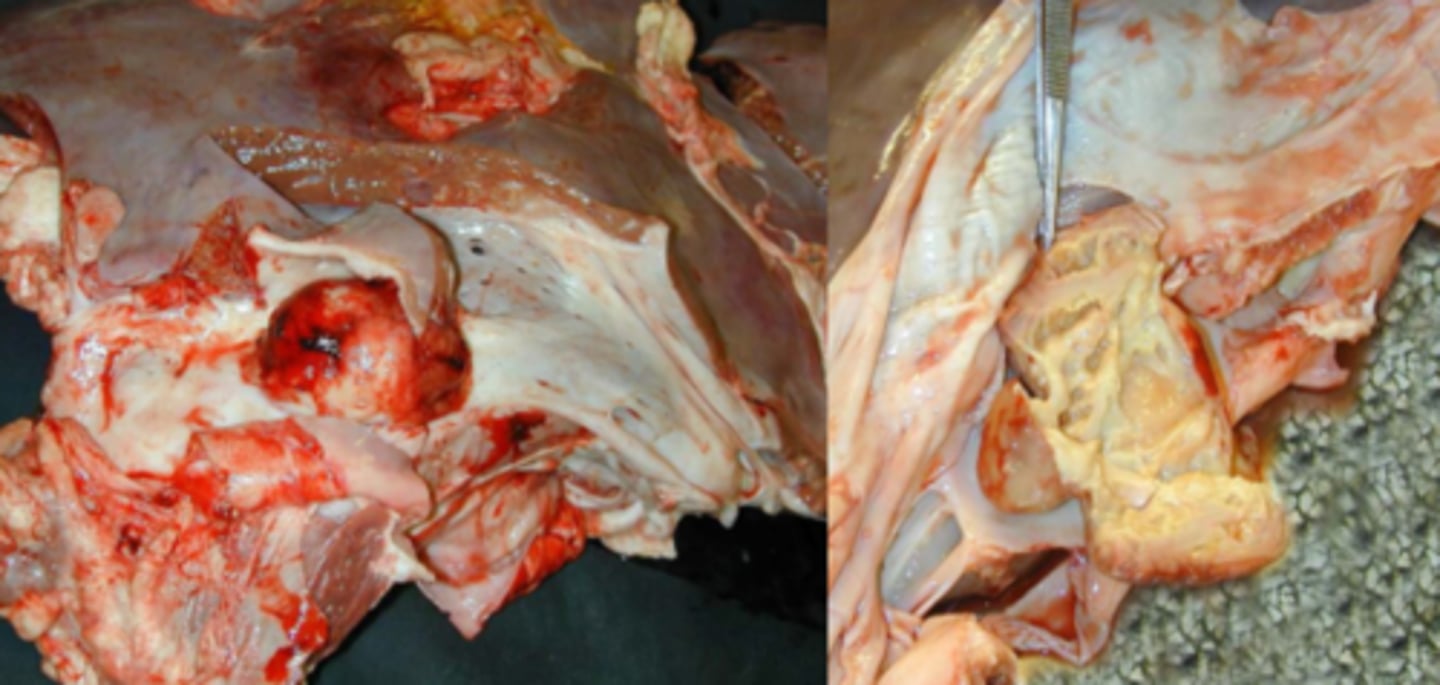

Kronisk, fokal hepatitis m. abscess formation og fibrinøs adhæsiv perihepatitis

(kan nemt forveksles med en subfrenisk absces)

Lever fra kvæg og diaphragma (d), hvad er den patoanatomiske diagnose?

Kronisk, lokal, subfrenisk absces m. fibrøs adhæsion

Lever fra kvæg og diaphragma (d), hvad er den patoanatomiske diagnose?

kronisk purulent og tromboserende endophlebitis

(venebetændelse)

Lever fra kvæg m. v. cava caudalis, hvad er den patoanatomiske diagnose?

Kronisk thromboserende endophlebitis med absces formation.

Opbrud af leverabsces til venen.

Lever fra kvæg m. v. heptatica, hvad er den patoanatomiske diagnose?